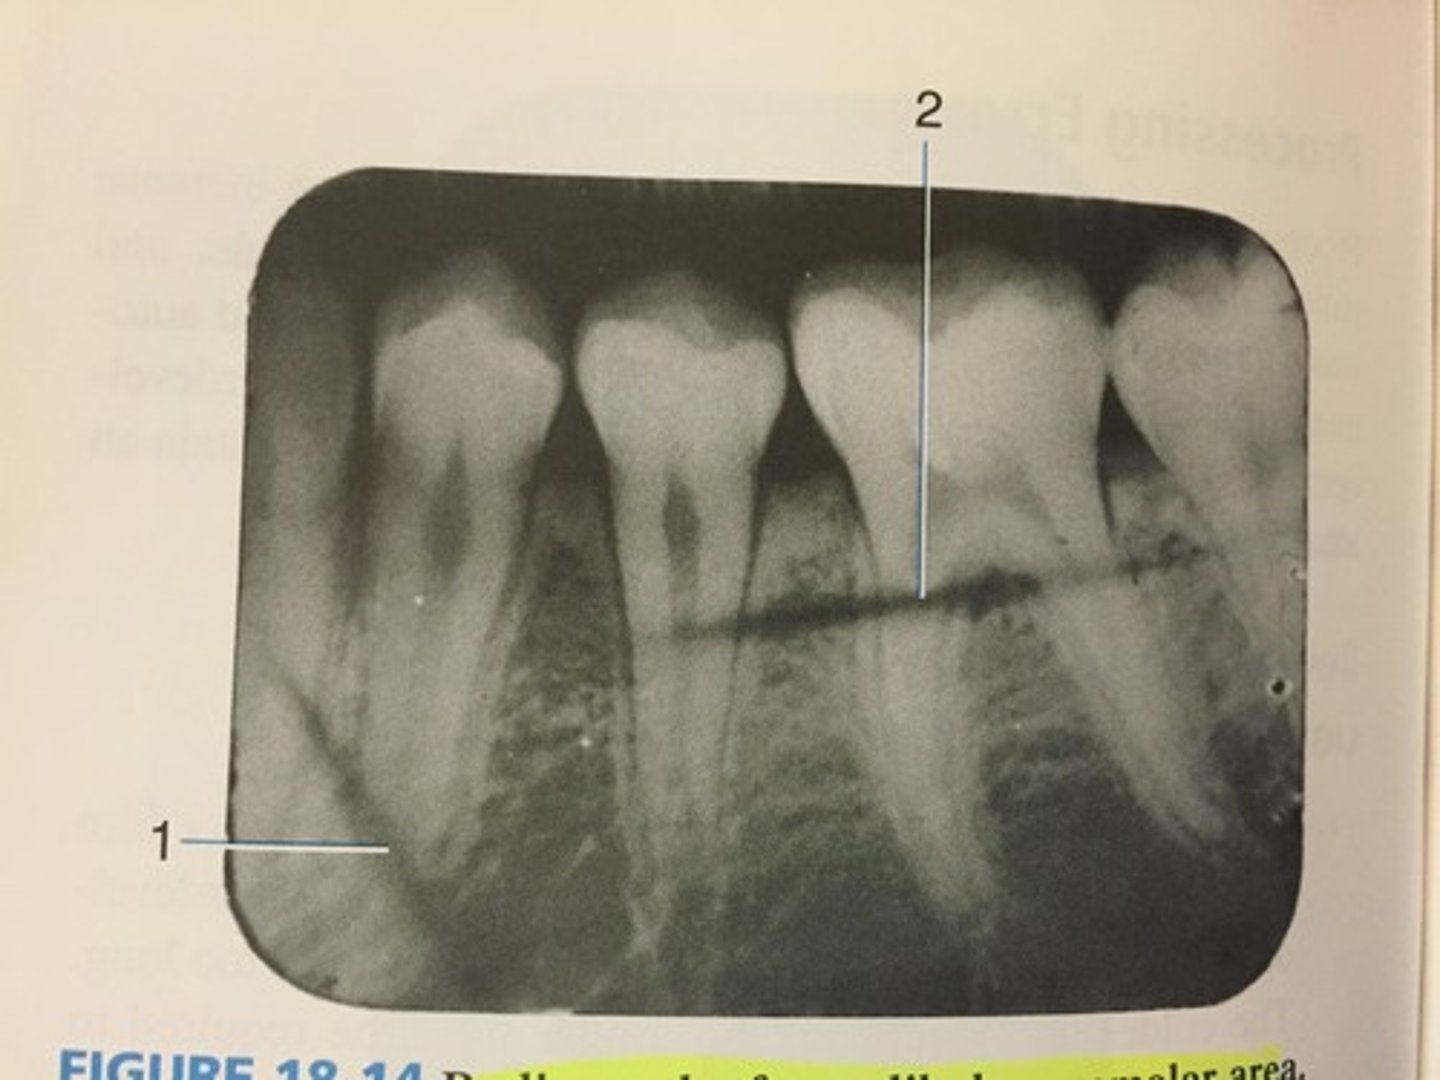

Incorrect film placement

Incorrect film placement can cause ?

Apical cut-off

Crown cut-off

Film too mesial

Film too distal

Overlapping

Slanted occlusal plane